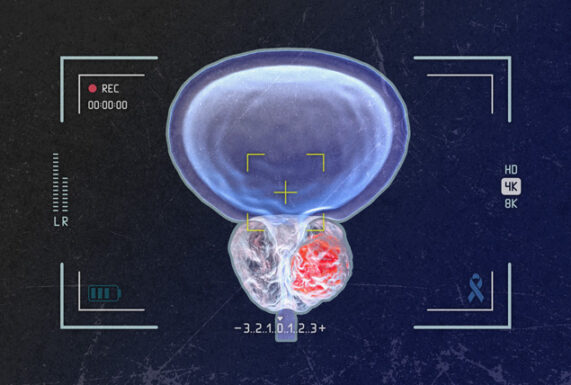

Continue ReadingRegain Confidence and Control Over Your Sexual Health. Expert Care by Dr. M. Prabhakar at Kalyani Kidney Care Centre

Best Andrology & Sexology Services in Erode | Dr. M. Prabhakar | Kalyani Kidney Care Centre Sexual health is a vital part of overall well-being, yet many men hesitate to seek help due to stigma or embarrassment. At Kalyani Kidney Care Centre, Erode, Dr. M. Prabhakar — a specialist in Andrology and Sexology — provides […]